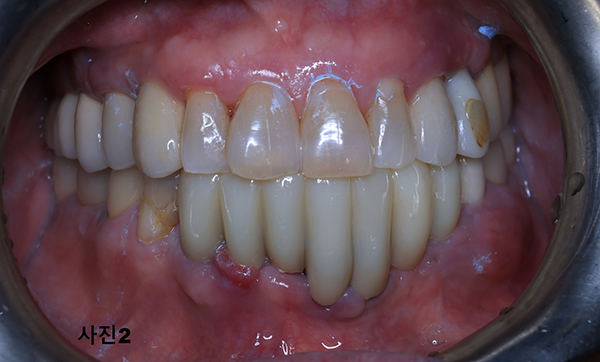

5개월후에 영구적인 티타늄과 지르코니아 보철물이 구강내 장착된 (사진5)와 x-ray(사진 6)모습이다.